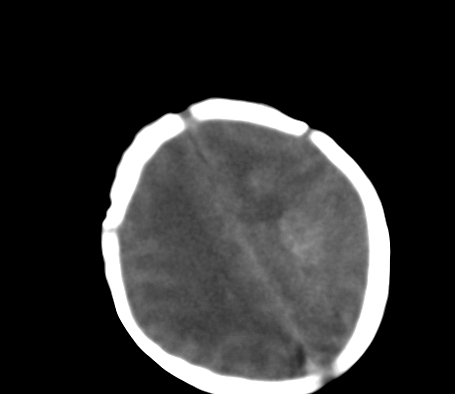

标题: PED0831:患儿,5天,是HIE吗?

患儿,出生时正常,第5天突然呕吐两次,无发热及抽搐。

片示:双侧大脑半球脑实质密度降低,皮髓分界尚清,左侧顶部脑沟内见铸形高密度影,脑中线结构居中。

2、hie并少量蛛网膜下腔出血。